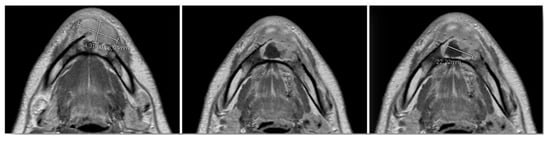

For oncological staging, the patient had orthopantomography, preoperative CT and MRI (Figure 6) of the head and neck, CT of the thorax, all with and without contrast, ultrasound echography of the neck and abdomen, a rhino-pharyngo-laryngeal fibroscopy and an angio-CT of the inferior limbs. No secondary lesions nor lymph node invasion were detected in preoperative staging.

Figure 6.

Preoperative MRI, multiple axial views. Vestibular extraosseous spread of the tumor was evident.

MRI with gadolinium-contrast represents a second-level examination essential for tumor staging, and in our case, the extent of the lesion through the anterior cortex erosion in the soft tissues of the chin was documented (Figure 6).